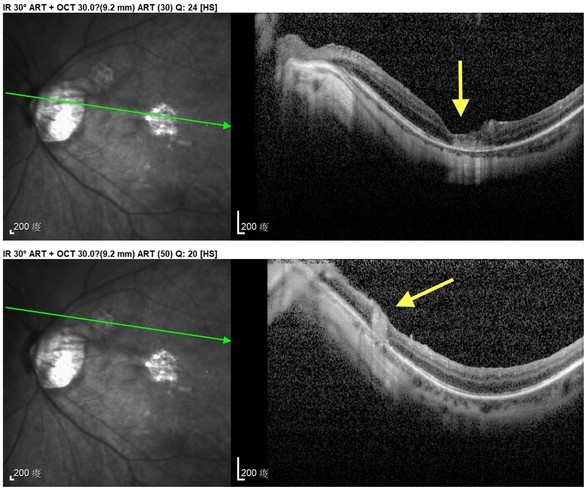

何明山主任在仔細檢查發現,張女士左眼同時有兩處大型黃斑部裂孔,分別為915與939微米,屬於少見的雙裂孔個案。何明山主任表示,得知張女士從過去一例成功治癒巨大黃斑部裂孔的報導中抱著希望,專程來到花蓮就診,針對此特殊情況,何明山主任採用創新雙重療法,以羊膜移植修補破洞,並輔以自體高濃度血小板血漿(platelet-rich plasma, PRP)注射,促進組織修復與裂孔癒合。

右圖:張女士經羊膜及PRP雙重療法後,兩處大型黃斑部裂孔順利癒合,張女士一解長期以來的困擾,開心表示終於能回歸日常生活。

手術過程中,何明山主任不僅修補黃斑部裂孔,更同步處理張女士眼中的白內障,術後追蹤顯示兩處破洞皆順利癒合,視力也漸漸改善,讓張女士很開心,終於不用再為視力所苦,而影響到生活。

花蓮慈院眼科部團隊已成功完成2例以羊膜及PRP雙重療法治療大型黃斑部裂孔,透過創新的治療方式,期望提供黃斑部裂孔病人新的治療選擇,幫助他們重見光明,並重拾自信與希望。